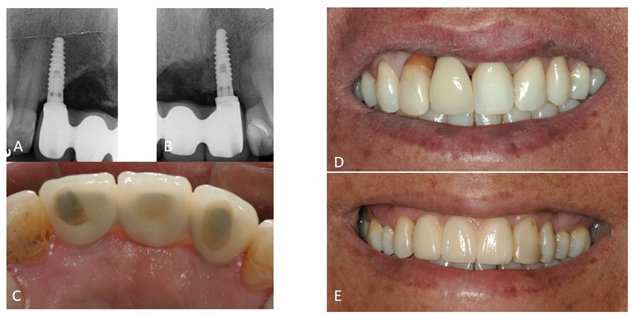

Após reavaliação, foi planejada a explantação do elemento 11 e exodontia do 12 e, após seis meses, planejado colocação de implante Cônico HI Implacil Osstem de 3,5x11mm e reabilitação. A paciente não aceitou passar por cirurgia para aumento da espessura e altura de tecido queratinizado, o que poderia melhorar a estética e favorecer a higienização. No entanto, a autonomia do paciente deve ser respeitada e as limitações devem ser explicadas. Nestes casos, o acompanhamento clínico personalizado e manutenções devem ser feitas regularmente para saúde e longevidade do sucesso da terapia de implantes.